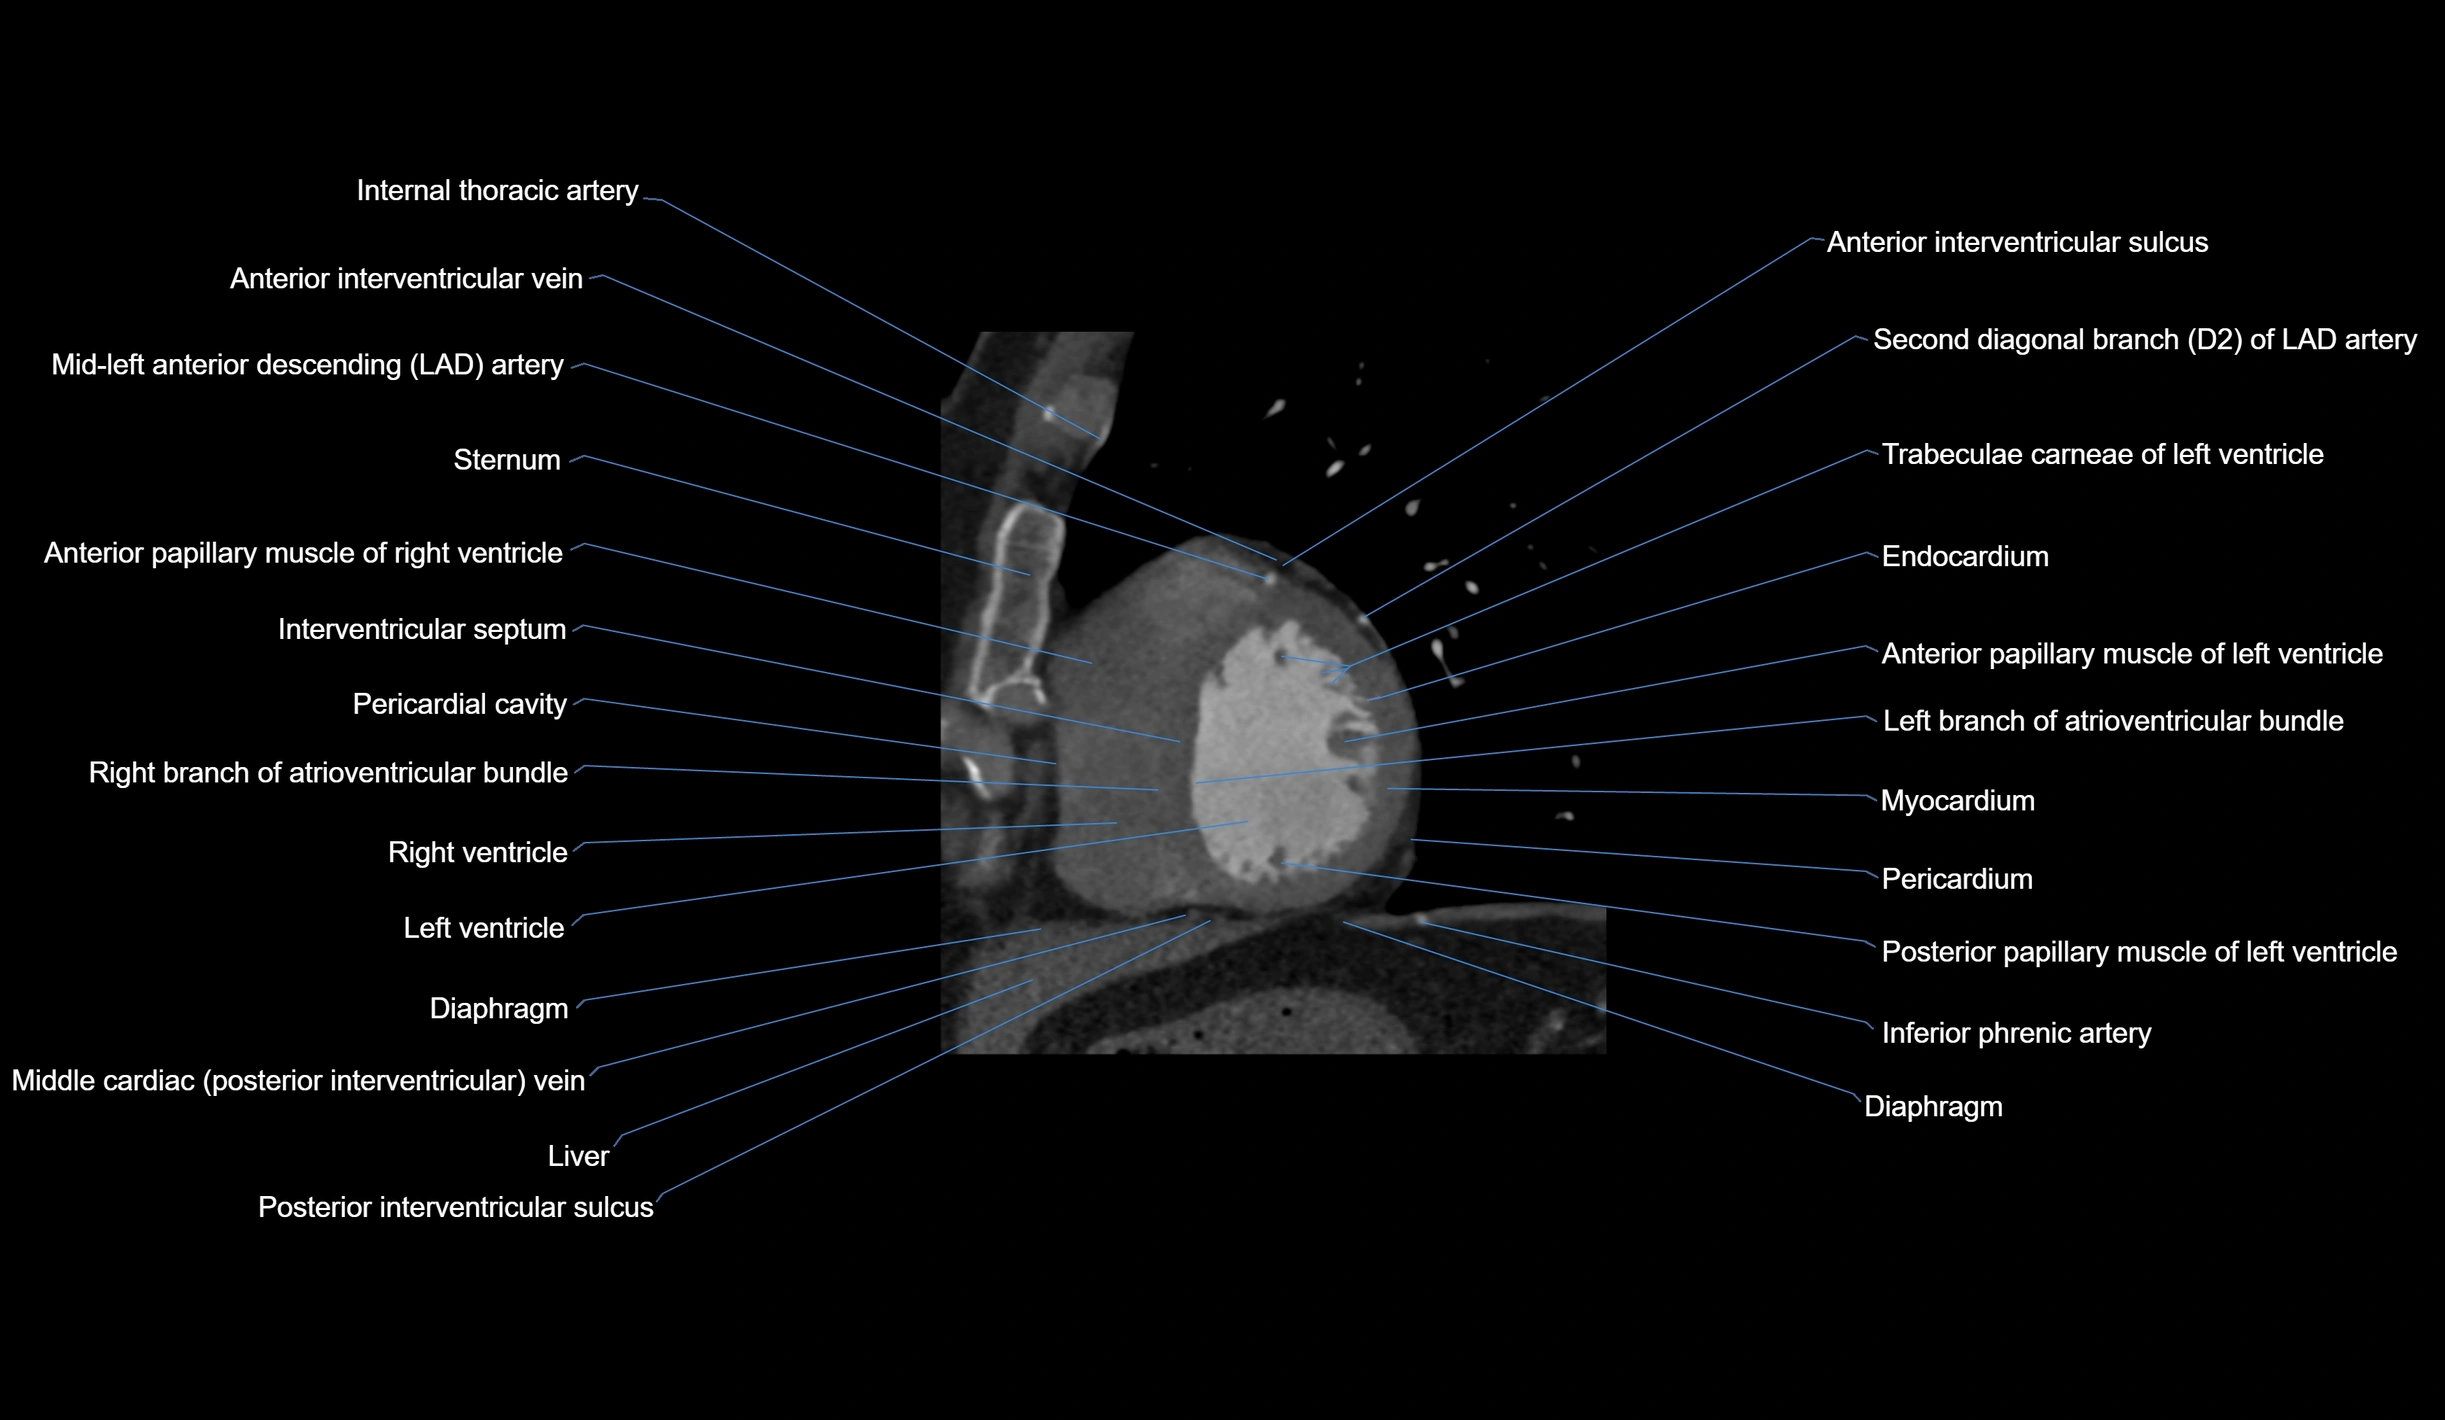

- Costal cartilages

- Diaphragm

- Endocardium

- Inferior phrenic artery

- Interventricular Septum

- Left branch of atrioventricular bundle

- Left ventricle

- Myocardium

- Pericardium

- Posterior interventricular sulcus

- Right branch of atrioventricular bundle

- Right ventricle

- Second diagonal branch (D2) of LAD

- Sternum

- Trabeculae carneae